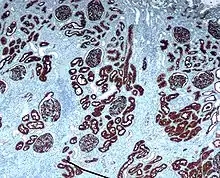

The renal cortex is the outer portion of the kidney between the renal capsule and the renal medulla. In the adult, it forms a continuous smooth outer zone with a number of projections (cortical columns) that extend down between the pyramids. It contains the renal corpuscles and the renal tubules except for parts of the loop of Henle which descend into the renal medulla. It also contains blood vessels and cortical collecting ducts.

The renal cortex is the part of the kidney where ultrafiltration occurs. Erythropoietin is produced in the renal cortex.